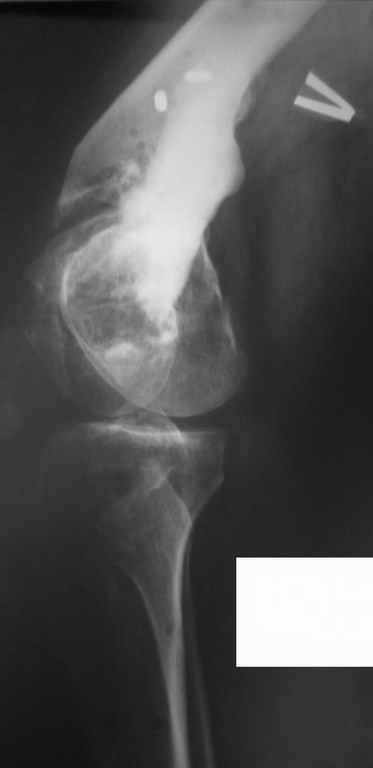

Был оперирован, среди прочего - остеосинтез DHS-фиксатором чреcшеечного перелома правого бедра, DCS-фиксатором остеосинтез оскольчатого чрезмыщелкового перелома левого бедра. Однако, в связи с развитием гнойного коксита были вынуждены убрать DHS-фиксатор и головку. Гнойный свищ правого тазобедренного сустава закрылся сразу после операции. Из-за вторичного смещения и поломки винтов пришлось удалить DCS-фиксатор и сращивать левое бедро внешней иммобилизацией. Прошло чуть более года. Пациент ходит с опорой на обе ноги,пользуется палочкой. Справа относительное укорочение 3см. Слева варус 33гр., тугой ложный сустав н/3бедра. Движения в коленных суставах почти в полном объёме.Перед нами встали вопросы, с чего начать? Протезирование правого ТБС? Восстановление опорности левой конечности? Воспользоваться-ли для этого интрамдулярным остеосинтезом гвоздём с блокированием с ретроградным введением? Стараться при этом восстановить полностью длину, или оставить на потом, на аппаратное решение? Или сразу попытаться использовать аппарат Илизарова? Но боимся потерять колено? Вопросов много.С благодарностью выслушаем все мнения.Заранее спасибоРахматуллин Ринат НургаяновичГКБ N 13 г.Уфа.